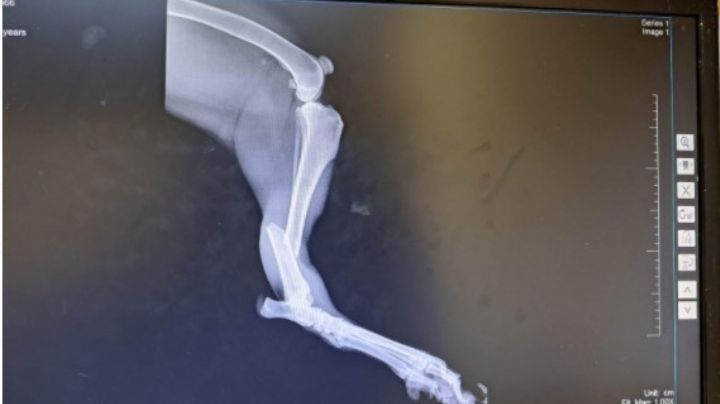

19/1/2023 | Luego de ser atropellado resultó con una fractura en su extremidad posterior, por lo que necesita una operación, de lo contrario podrían amputarlo